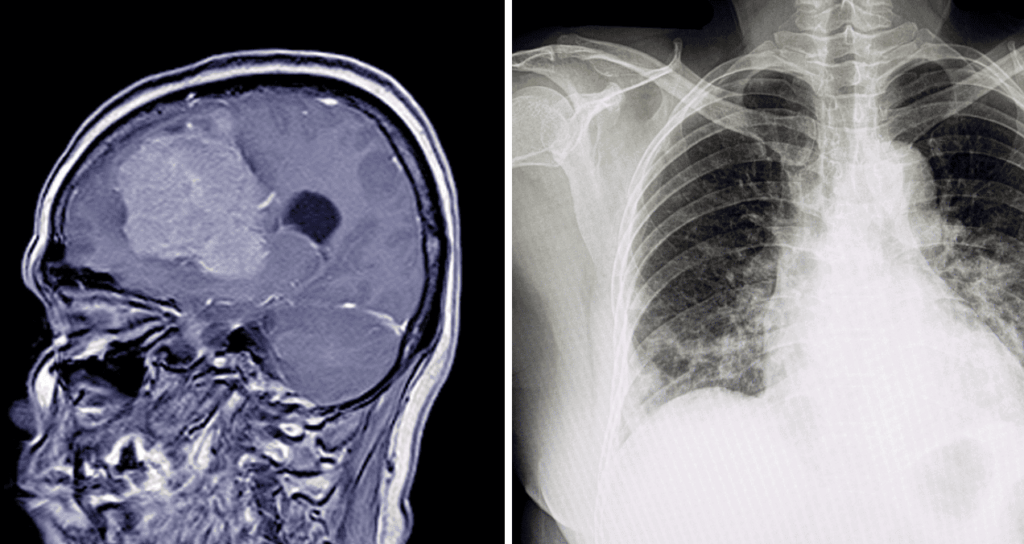

El diagnóstico suele basarse en los síntomas y en la altitud alcanzada. En casos graves, los médicos pueden usar radiografías de tórax, medición de oxígeno en sangre o estudios cerebrales.

Ocurre cuando el cerebro acumula líquido. Puede causar:

Es una acumulación de líquido en los pulmones y representa una de las principales causas de muerte asociadas al mal de altura.